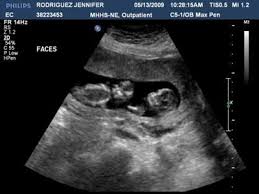

In fact doctors may be able to determine the sex of your baby through an ultrasound. Since an ultrasound creates an image of your baby it can also reveal the sex of your baby. For most fetuses with xy chromosomes the genital ridge starts to lengthen into a penis by week 11. You can come in for gender determination starting at 14 weeks 0 days.

14 weeks is a little early to be totally accurate but then again it is much easier to identify a boy earlier on. The gender of your baby is revealed at your second scan between 18 and 21 weeks but there s another test people use to determine if it s a boy or girl credit. Most doctors schedule an ultrasound at around 18 to 21 weeks but the sex may be determined by ultrasound. If you are having a gender reveal party we strongly recommend having your ultrasound at least 1 week before your event.